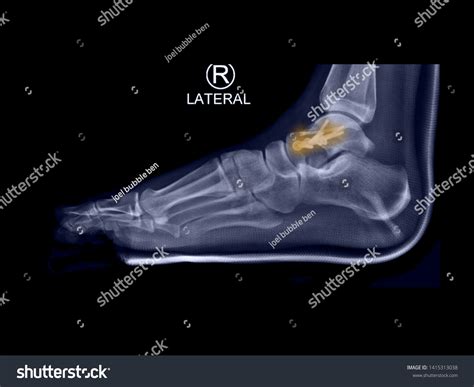

To determine the severity of a shattered talus bone, orthopedic surgeons rely on high-resolution imaging. Standard X-rays provide the initial view, but they are rarely enough to see the full extent of a comminuted fracture. A CT scan is almost always required to map out the fragments in 3D, allowing the surgeon to plan the reconstruction. MRI scans may also be used to evaluate the health of the soft tissues and the status of the blood supply to the bone fragments.

X-Ray Initial assessment of major displacements.

CT Scan Detailed mapping of bone fragments and joint surface damage.

Because the talus relies on a delicate network of blood vessels, surgery for a shattered talus bone is highly specialized. The surgeon must carefully navigate the area to avoid further damaging the remaining blood supply. The goals of surgery are to:

1. Bring the bone fragments back into their anatomical position (reduction).

2. Use internal fixation devices, such as small plates and specialized screws, to hold the bone together while it heals.

3. Restore the smooth contours of the joint surface to prevent future arthritis.